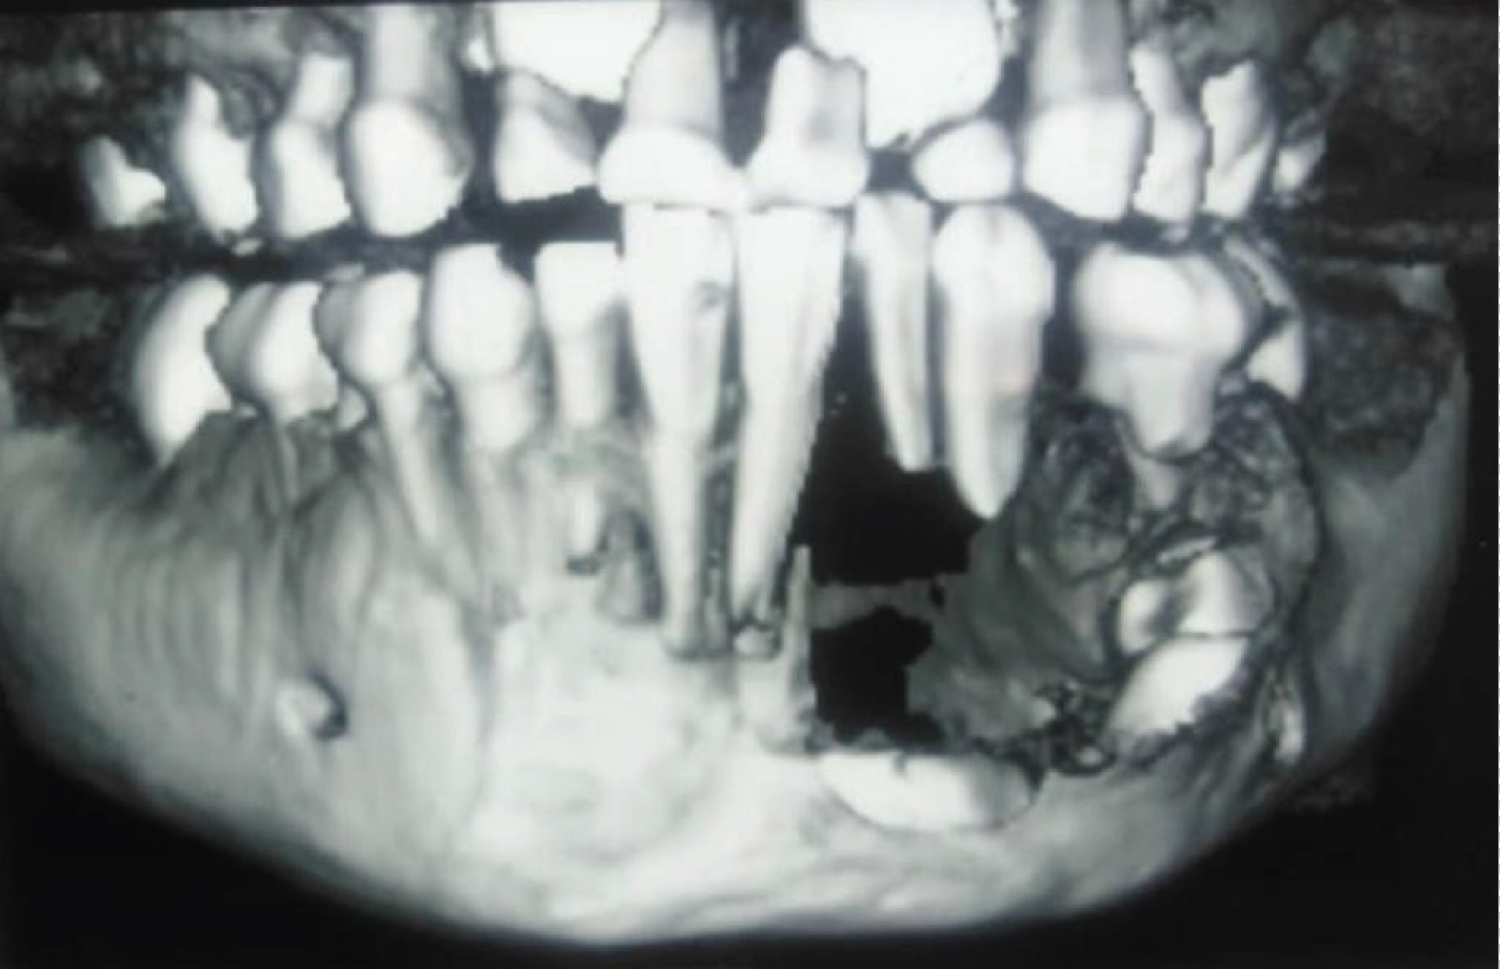

An 8-year-old African descent boy presented to the department of oral and maxillofacial surgery at Sharque Alnil Hospital complaining of swelling and lost teeth on the left side of the lower jaw for three weeks. No history of pain fever, loss of weight or night sweats. On examination, the face was symmetrical and no palpable lymph nodes. Intraorally, expansion of buccal and lingual cortices was seen on the left side of the lower jaw at the area of A, B, C, D, and E deciduous teeth with grade 2 motilities of A, B, C and D teeth and loss of tooth number D. no occlusal interference, no ulceration on the overlying mucosa. On the radiographic image (Figure 1 and Figure 2) Ill-defined radiolucency in the lower left side of the jaw extending from the first deciduous incisor to the second deciduous molar was evidence, permanent successors were within the tumor and were pushed downward and the lower border of the mandible was intact. In differential diagnosis, dentigerous or periapical cysts were thought. A biopsy was taken which microscopically showed interlacing bundles of oval cells with adjoining fibro-collagenous connective tissues and reactive bone trabeculae with no epithelial lining or granuloma or malignancy and that is revealed a benign spindle cell lesion. Further immunohistochemistry was recommended for verification and rule out of other possibilities and results were negative for desman, SMA, CD68, CD34 and S100, and results consistent with fibromatosis. After having to discuss the treatment plan with parents, the treatment plan was formulated. In order to preserve the permanent teeth, the young patient underwent conservative surgical curettage and extraction of loose deciduous teeth. A prosthesis was constructed to replace the extracted teeth and to cover the bony defect and the patient was subjected to periodic follow-up clinically and radio graphically. After 8 months postoperatively, the panoramic image did not show any evidence of recurrence. Moreover, the permanent teeth in the area of the surgery appeared to erupt uneventfully except the left lower canine (Figure 3). The patient is and closely observed to assure no recurrence and normal eruption of the permanent teeth.

Plain image of the affected bone shows well-defined radiolucent lesion which appears as unilocular or multilocular with partially sharp or diffuse border without sclerotic margins [10] which is in agree with our findings that exhibits a unilocular radiolucent lesion with ill-defined diffuse margins on the panoramic view, while the 3 D Con beam CT scan showed an obvious buccal and lingual cortexes defects. Floating teeth without alveolar bone support associated with root resorption is a common finding that agrees with our case. For precise assessment of the tumor which is mainly soft tissue, it is better to order MRI, to see the exact expansion of the tumor and it is also suitable for surgical planning [11].